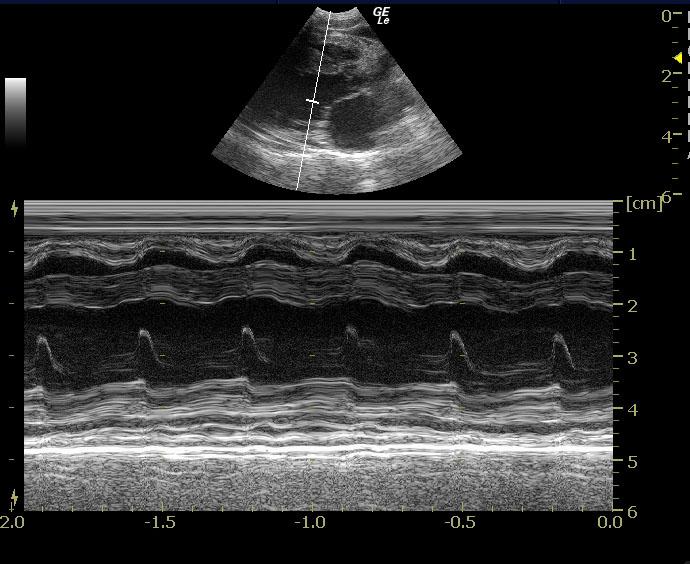

The cardiac presentation presented right and left sided overload. Septal and free wall thicknesses were mildly excessive. Mitral insufficiency was noted. Smoke was noted in the left atrium. Pleural effusion was also noted along with slight pericardial effusion. The right atrium was mildly enlarged as well. The left ventricular septum and free wall were stiff. Subnormal contractility was noted. This is most consistent with restrictive cardiomyopathy.

Restrictive cardiomyopathy. Left sided congestive heart failure. Pleural effusion and pericardial effusion.